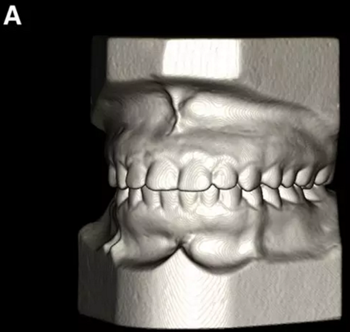

患者的上頜骨和下頜骨研究模型在最大牙尖交錯位時確定和數字化(圖2,A),作為咬合指導(咬合指導)。該數字化咬合指導在齦緣周圍進行數字化修剪,以便在CBCT掃描上可以更好得可視化(圖2,B)。

圖2. A,咬合時對象研究模型的右側舌側視圖掃描將作為未來指導;該指導稍后用于將懸浮的下頜骨配對到修剪的上頜骨;B,左側舌側視圖的數字化修整牙合引導。